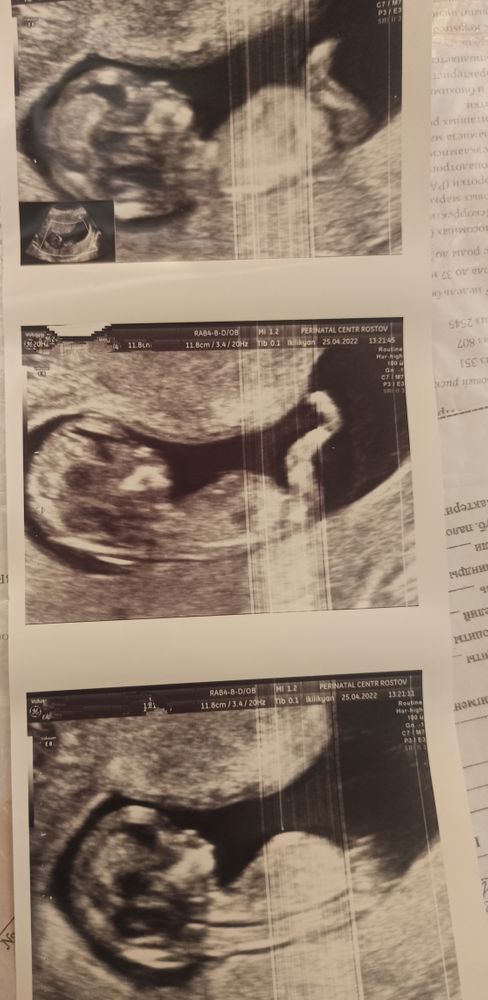

Срок 15,2 , на скрининге в 11,5 тоже предполагали 90% мальчик

Хочу на выходных объявить родным пол ребенка. Все очень ждут мальчика💙 Доктор сказал 100% сын. А очень рада, но очень боюсь ошибки... Хотелось бы послушать ваше мнение. Я даже маме пока не сказала... Хотя хочется уже всем объявить о своем счастье💞

Смотрю, Вы пост переименовали))) Парень у Вас, видно же))) Вон мошонка и перчик сверху😊